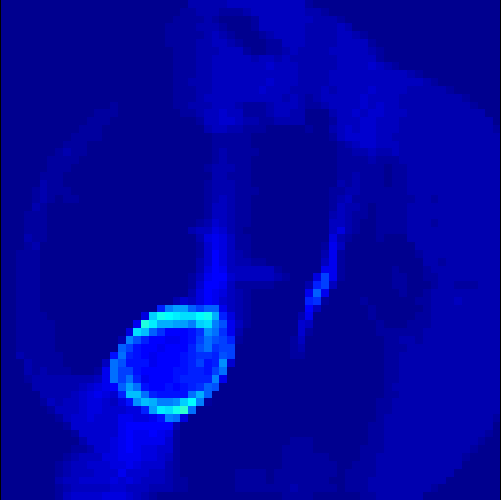

5.2 Monte Carlo Simulation

In order to test the behaviour of the proposed method in a more realistic, random-based test case, we performed a Monte Carlo simulation for dynamic SPECT imaging. First, we created a simple image phantom consisting of an outer and two inner circles which represents the structure of the region of interest (see figure 8(a)). Within those regions we assumed concentration curves over a time period of 90 time steps as displayed in figure 8(b). Based on the tracer intensity in an image frame at each time step, we created a variable number of random decay events (where the number is proportional to the average concentration in one pixel in the whole image frame per time step) with a probability proportional to the concentration in every subregion. They are detected by a virtual double head gamma camera rotating around the patient by 46 degrees per time step, which consists of 374 detector bins. Every simulated decay event is projected onto the scanner and counted by the corresponding detector bin.

In two different tests we fixed the number of events counted by the detector equal to (resp. ) times the average concentration in one pixel. The resulting sinogram images of the accumulated counts in each bin are shown in figure 9.

Based on the sinogram data we applied the proposed algorithm in order to reconstruct the original image sequence. The results for both test cases are shown in figure 10.

As one can see, the method is able to reconstruct the regions properly, even in case of a low count number. Within a number of iterations (average of 100 outer and 10000 inner iterations), the algorithm presents a reasonable reconstruction of the region of interest and the corresponding regional tracer concentration curves. Here, the parameters were not optimized as in the case of the synthesized data sets in the previous section, but kept fixed as , and . With futher optimized parameter values one could possibly provide even better results.